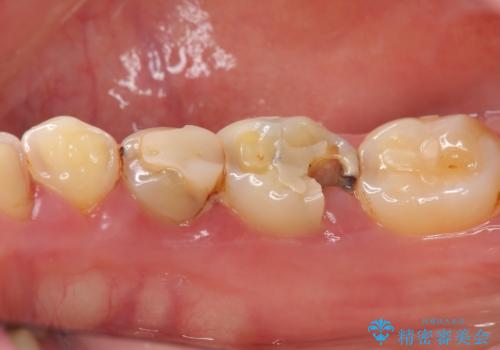

大きい虫歯 根管治療〜オールセラミッククラウン